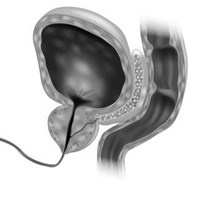

Острый эпидидимит — это воспаление и боль, длящиеся более б нед, на фоне увеличения размеров придатка яичка.В большинстве случаев эпидидимит развивается в результате попадания инфекции восходящим путем из мочеиспускательного канала,